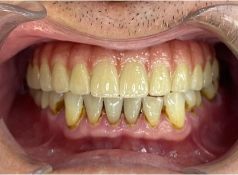

• Tình trạng răng trước đây:Mất nhiều răng ở hàm trên, tiêu xương hàm.

• Bác sĩ chỉ định:Cấy ghép Implant All On 4 hàm trên.

• Cấy ghép Implant All On 4 hàm trên

• Phục hình răng sứ trên Implant